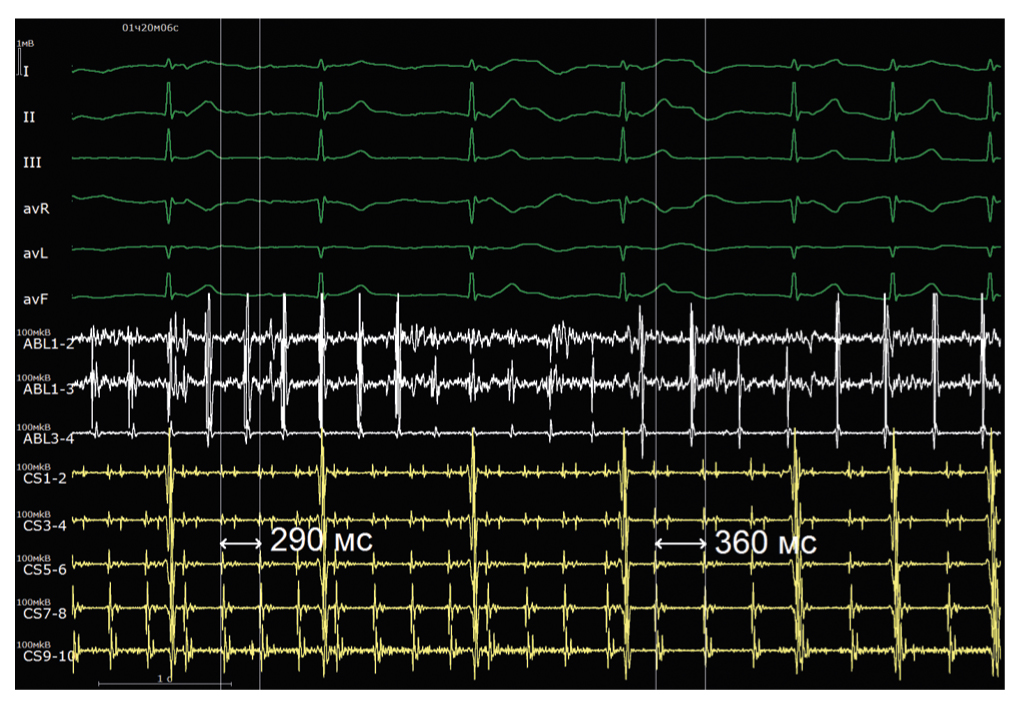

При анализе активационной карты визуализируется циркуляция возбуждения вокруг правых и левых легочных вен (рис. 3, а). Выполнена серия линейных воздействий на крыше, соединяющая правую верхнюю и левую верхнюю легочные вены (рис. 3, б). Абляция выполнялась при следующих параметрах: мощность 32 Вт, температура до 44°С, индекс абляции 460 при воздействии по передней стенке, 380 — по задней стенке. После завершения линии отмечается нарастание цикла тахикардии до 360 мс (рис. 4).

Рис. 4. Интраоперационная электрограмма, где I–III, aVL, aVR, aVF, V1–V6 — отведения электрокардиограммы, ABL (1–4) — запись электрограмм аблационного электрода, CS (1–10) — запись электрограмм с электрода, размещенного в коронарном синусе. Продемонстрировано нарастание длины цикла тахикардии с 290 до 360 мс во время радиочастотного воздействия. / Fig. 4. An intraoperative electrogram, where I–III, aVL, aVR, aVF, V1–V6 are electrocardiogram leads, ABL (1–4) is recording of ablation electrode electrograms, CS (1–10) is recording of electrograms from the electrode placed in the coronary sinus. An increase in the tachycardia cycle length from 290 ms to 360 ms during radiofrequency ablation is seen.